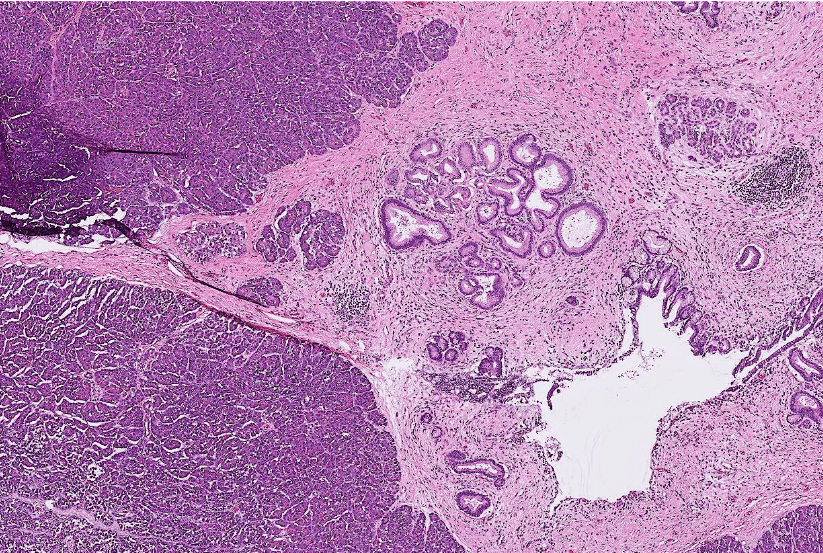

lung adenocarcinoma

colon cancer

endometrial cancer